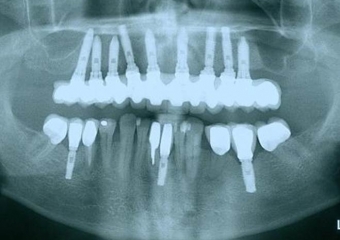

Raio X dos implantes

Raio X da prótese fixa em porcelana superior